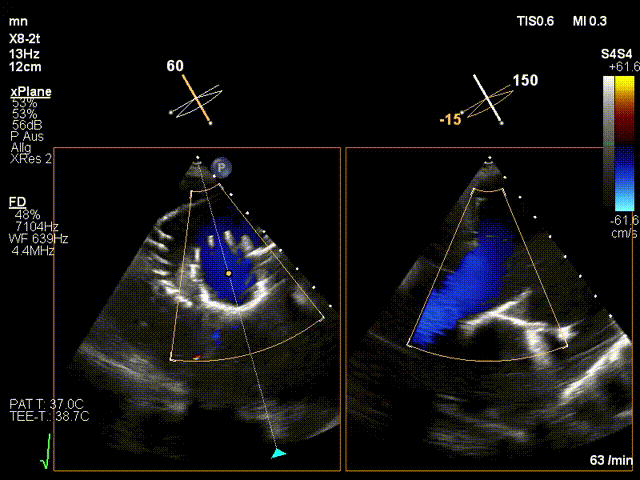

LuX-Valve Plus經(jīng)血管三尖瓣置換系統(tǒng)本次“出海”圓滿完成,術(shù)后Jörg Hausleiter教授對(duì)LuX-Valve Plus經(jīng)血管三尖瓣置換系統(tǒng)的器械性能和治療效果大為稱贊,認(rèn)為LuX-Valve Plus的手術(shù)體驗(yàn)非常好。術(shù)后即刻超聲顯示三尖瓣反流消失,血流動(dòng)力學(xué)改善顯著,患者恢復(fù)快。Anson Cheung教授也肯定了LuX-Valve Plus術(shù)中操作的便捷性,認(rèn)為LuX-Valve Plus容錯(cuò)率高,對(duì)術(shù)中影像的依賴較小,后期希望可以更多的應(yīng)用LuX-Valve Plus三尖瓣置換系統(tǒng)于臨床實(shí)踐,讓更多的三尖瓣重度反流患者盡早獲益,改善預(yù)后。